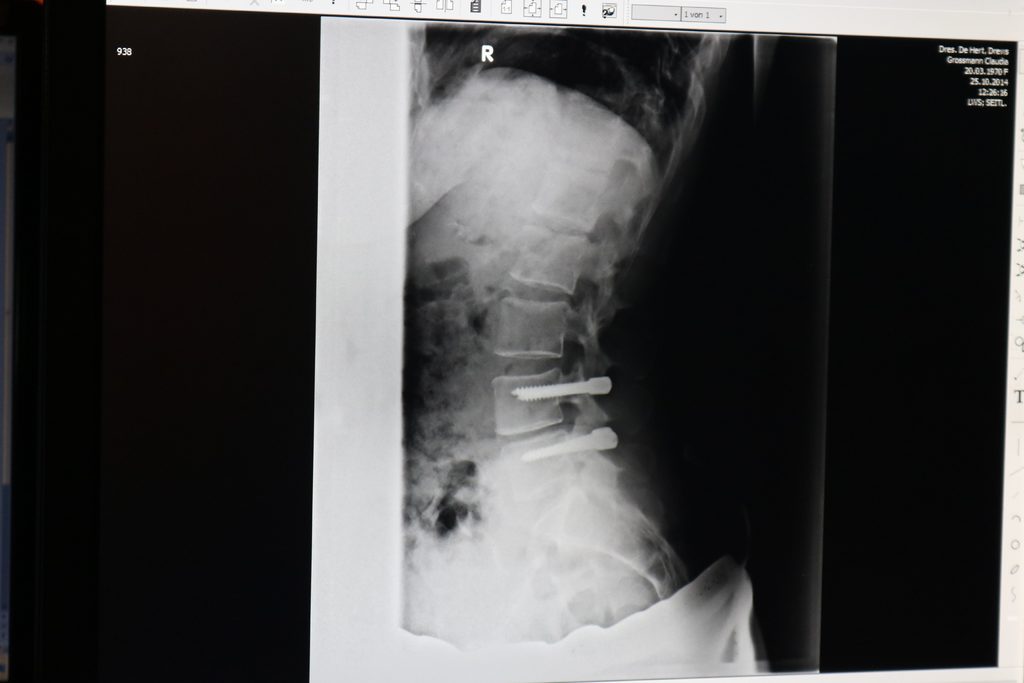

In der Orthopädie sind Röntgenaufnahmen unverzichtbarer Bestandteil der Diagnostik. Veränderungen des Knochens wie Brüche, Tumore oder Entzündungen, sowie Abnützungen der Gelenke (Arthrosen) können diagnostiziert werden.